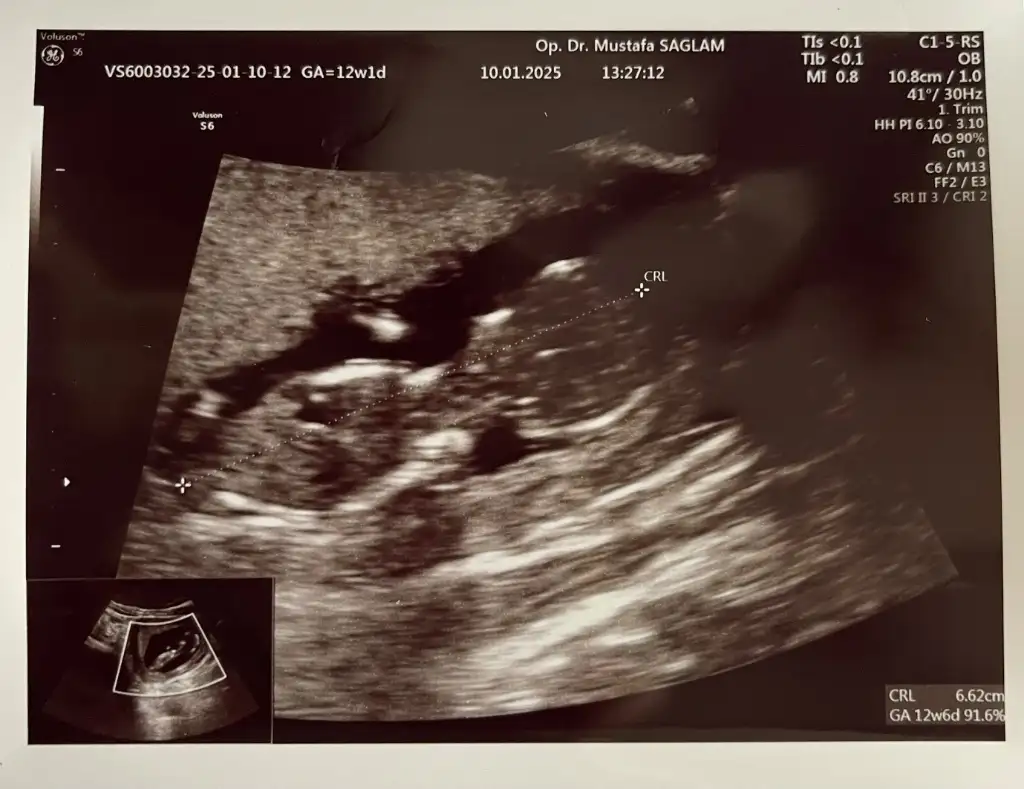

D Dnz007 Üye Kayıtlı Üye 21 Aralık 2024 140 9 11 35 ANTALYA 10 Ocak 2025 Konu Sahibi Konu Sahibi kderysra #81 Surayaldz .!.: Başka fotoğraf varmı canım çok belli değil fotoğrafta Genişletmek için tıkla... Buda 12+2 haftalık burda tahmininiz var mı acaba? Eklentiler IMG_7083.webp 39,9 KB · Görüntüleme: 32

Surayaldz .!.: Başka fotoğraf varmı canım çok belli değil fotoğrafta Genişletmek için tıkla... Buda 12+2 haftalık burda tahmininiz var mı acaba?

Surayaldz Üye Kayıtlı Üye 28 Eylül 2024 359 310 23 24 11 Ocak 2025 Konu Sahibi Konu Sahibi kderysra #82 Dnz007 .!.: Buda 12+2 haftalık burda tahmininiz var mı acaba? Genişletmek için tıkla... Kıza benziyor sanki canım

Dnz007 .!.: Buda 12+2 haftalık burda tahmininiz var mı acaba? Genişletmek için tıkla... Kıza benziyor sanki canım

Sabrina01 Ailem Benim Dünyam Anneler Kulübü Kayıtlı Üye 22 Nisan 2016 484 579 103 5 Şubat 2025 Konu Sahibi Konu Sahibi kderysra #84 Dnz007 .!.: Buda 12+2 haftalık burda tahmininiz var mı acaba? Genişletmek için tıkla... Bilmiyorum bana de kız diye tahmin ediyorum.. sağlıkla kucağına alırsın inşaALLAH

Dnz007 .!.: Buda 12+2 haftalık burda tahmininiz var mı acaba? Genişletmek için tıkla... Bilmiyorum bana de kız diye tahmin ediyorum.. sağlıkla kucağına alırsın inşaALLAH